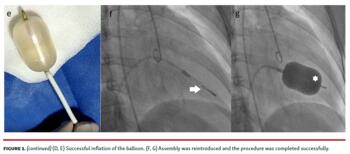

A 52-year-old female patient with severe rheumatic non-calcific mitral stenosis presented to the emergency department in New York Heart Association class IV heart failure. Her mitral valve area was 0.8 cm2 and mean diastolic gradient was 18 mmHg. Emergency percutaneous balloon mitral valvuloplasty (BMV) was planned with a reused Inoue balloon. The balloon was checked for damage prior to insertion. After successful entry into the left ventricle, we detected inflation failure secondary to contrast extravasation from the distal tip of the balloon (Figure 1A). Due to lack of a backup balloon and the patient’s refusal for emergency surgery, we attempted an off-label improvisation to correct the leak. The leak occurred through a single small rent at the tip. We advanced a 2 x 9 mm Sprinter non-compliant coronary balloon (Medtronic) over a 0.014" coronary guidewire through the central lumen of the Inoue balloon (Figure 1B and Figure 1C). Inflation of the non-compliant balloon to 20 atm sealed the rent (Figure 1D). After confirming successful inflation and deflation of the Inoue balloon externally (Figure 1E), the entire assembly, including the NC balloon (arrow), was reintroduced and the procedure was completed successfully (Figure 1F and Figure 1G; Video 1). The patient is doing well 10 months post procedure.